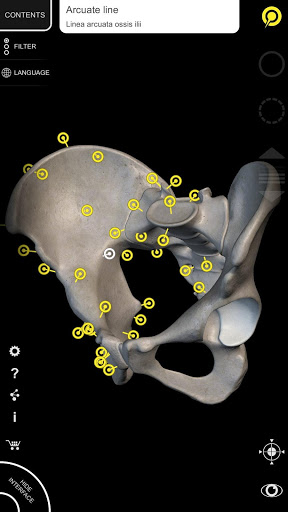

"Anatomy 3D Atlas" vous permet d'étudier l'anatomie humaine de manière simple et interactive.

Grâce à une interface simple et intuitive, il est possible d'observer chaque structure anatomique sous n'importe quel angle.

Les modèles anatomiques 3D sont particulièrement détaillés et avec des textures jusqu'à une résolution de 4k.

La subdivision par régions et les vues prédéfinies facilitent l'observation et l'étude de parties individuelles ou de groupes de systèmes et les relations entre différents organes.

MODÈLES ANATOMIQUES 3D

• Système musculo-squelettique

• Faites pivoter et zoomez chaque modèle dans l'espace 3D

• Option pour masquer ou isoler un ou plusieurs modèles sélectionnés

• Filtrez pour masquer ou afficher chaque système

• En sélectionnant un modèle ou une épingle, le terme anatomique associé apparaît